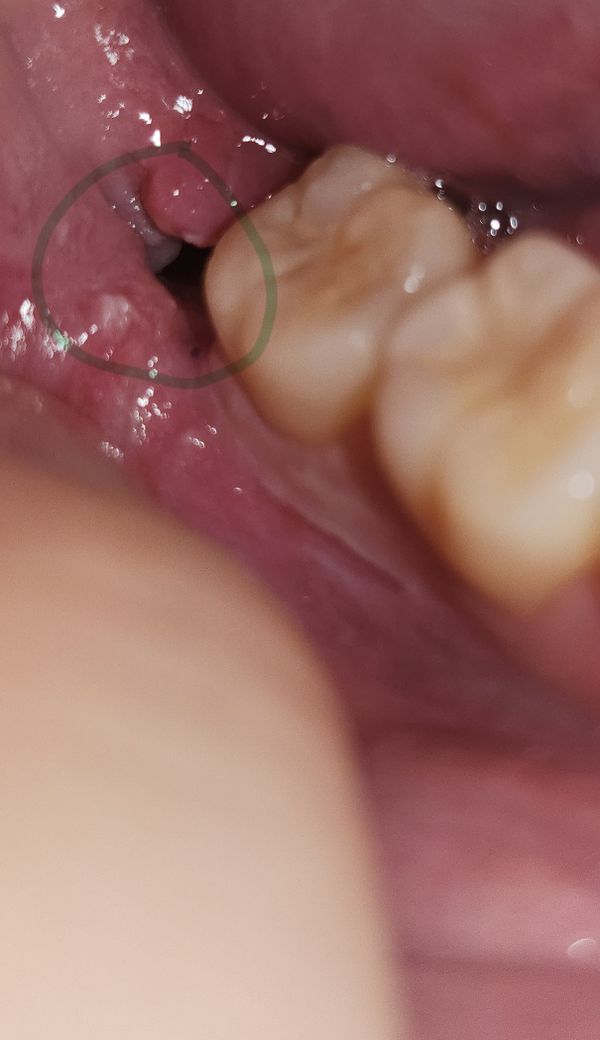

사랑니 실밥 제거 후 검은색 무언가 보여요

안녕하세요! 사랑니 실밥 제거한 지 8일차 (어제 실밥 뽑았음)입니다.

거울을 들여다보니 발치한 부분 안 쪽에 검은색 무언가가 보이는데 혀로 만져보니 느껴지는 건 없어서 실밥은 아닌 듯 합니다. 범위도 약간 광범위하게 있어서요. 그리고 동굴처럼 그림자는 아닌 것 같습니다! 사진상으로는 그럴 수 있는데 후레쉬로 비춰보면 안에가 명확하게 보여요.

피딱지 인 걸까요? 자연스럽게 아무는 과정일까요? 답변 부탁드립니다 감사합니다 선생님!

• 1번 째 사진

사진에 보이는 부분은 치아가 잇던 공간이 어두워서 까맣게 보이는 겁니다. 큰 문제가 잇는건 아닙니다.

뭔가 있는 것은 아니고 단지 빈 공간으로 보입니다 발치 후 잇몸뼈가 차오르기까지는 시간이 많이 걸립니다